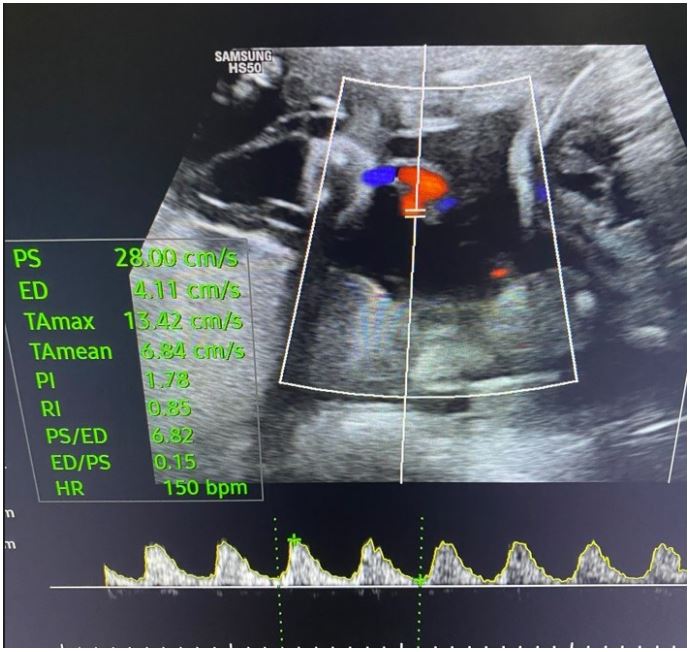

Transabdominal ultrasound identified intrauterine MCMA twin pregnancy. The right ovary measured 14x6.5x9.7 cm with multiple peripherally displaced ovarian follicles resembling a string of pearls (Figures 3 and 4). The left ovary measured 12x7x9.1 cm also with peripheral follicles and stromal oedema (Figure 5). In both ovaries, there was an absent doppler flow. In the region of the right adnexa, there was a collection of free fluid up to 8 mm (Figure 3). Umbilical arterial (UA) Doppler assessment was used in the surveillance of fetal well-being, which showed good fetal condition (Figures 6 and 7).

Figure 6: Umbilical arterial (UA) Doppler assessment of the first twin shows good fetal condition.

Figure 7: Umbilical arterial (UA) Doppler assessment of the second twin shows good fetal condition.